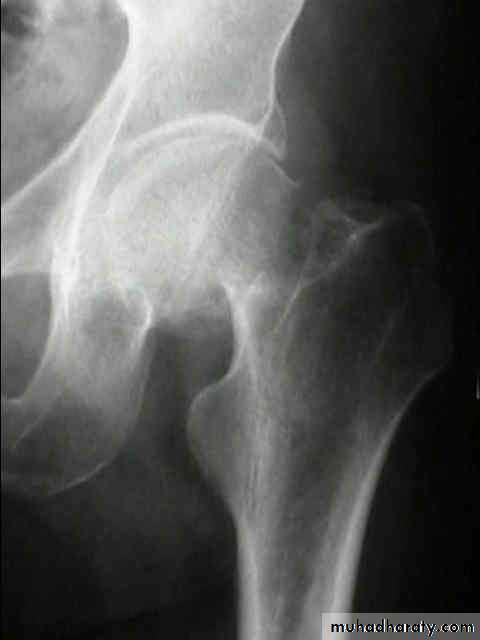

Inter-trochanteric fractures (extracapsular fracture)

.It is extra capsular fracture occurs in elderly..Unite quite easily and seldom cause a vascular necrosis.

The crack runs up between the lesser and greater trochanter.

Pathological anatomy divided into:

Stable:Unstable are those where

a. posteriomedial cortex is shattered.b. poor contact between fracture segment.

Radiological examination

2 typesStable.

Unstable.